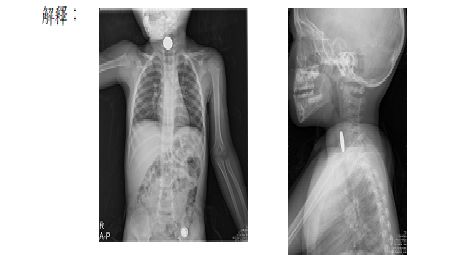

Chest AP (including Abdomen兒科)

通常用於兒科,需要胸腹一起看,但還是以胸部為主。

誤食異物,要看是在消化系統的哪一段。

誤食異物的小朋友,可先瞭解誤食的是何物,也先確認身上是否有會顯影的東西,先排除之後再照相。有時需要照neck lateral projection,可先瞭解異物是卡在哪裡?在開刀之前會再來照一次,確認異物是否還卡在喉嚨,還是已經到腸胃道了,這與之後醫師的處置完全不同。